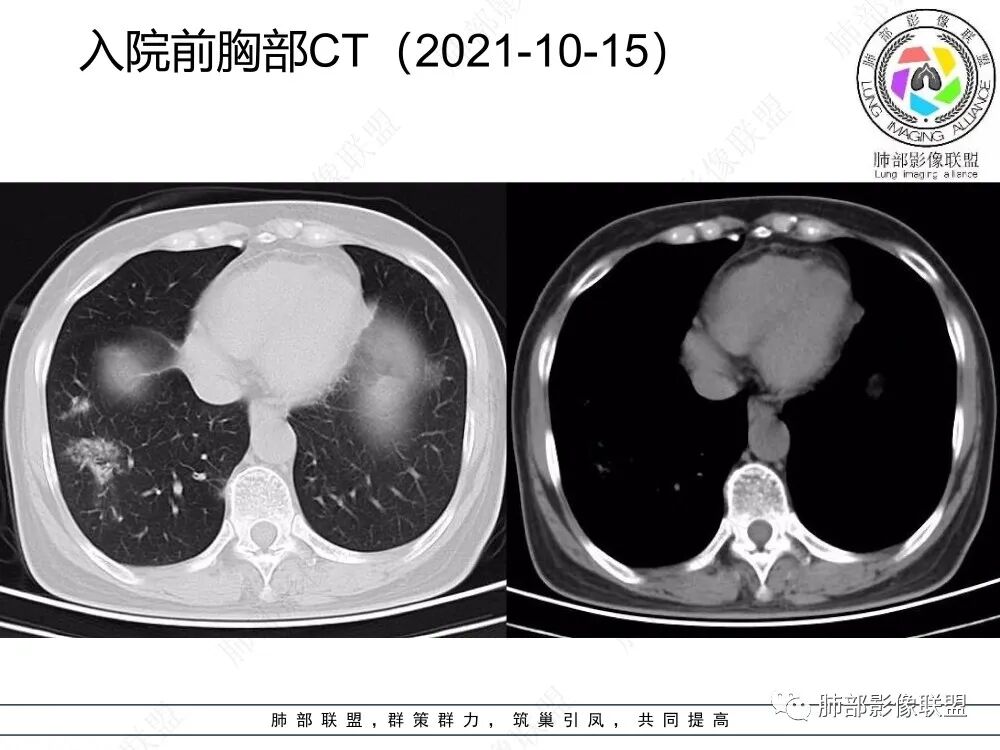

2、CT表现为两肺下叶结节影、斑片影、磨玻璃影,沿支气管血管束分布,部分支气管壁显示增厚。粗略一看部分病灶内似可见“细网格影”,但是仔细观察,可发现此“细网格影”不同于我们常见的“细网格影”,尤其是右肺下叶病灶,可以观察到病灶内部的网格上有高密度结节感或颗粒感,部分层面见“反晕征”,且反晕的边缘亦可观察到结节感。未见胸腔积液。

3、反晕征又称为环礁征、环岛征或环状珊瑚岛征,表现为中心磨玻璃影,周围为高密度影环绕,最初被认为是隐源性机化性肺炎(COP)的特征性表现之一,但随后不断有研究发现反晕征亦可出现在多种感染及非感染性疾病、肿瘤及非肿瘤性疾病中。反晕征的常见疾病谱有:①感染性疾病:肺孢子菌病、侵袭性肺真菌感染、肺结核、病毒性肺炎;②非感染性疾病:肺淋巴瘤样肉芽肿、韦格氏肉芽肿、 结节病、机化性肺炎(包括隐源性和继发性)、肺栓塞;③肺腺癌以及肺肿瘤治疗后。

4、本例急性病程,发热、咳嗽,结合影像多发磨玻璃影表现首先会考虑到感染性病变:①病毒性肺炎,病灶间质分布为主,常较弥漫,外围多见,临床症状重且常与影像表现同步;②支原体肺炎,病变多为1-2叶段、少数多叶段分布,支气管壁弥漫较均匀增厚,可见树芽征、腺泡结节及树雾征;③肺结核,上叶尖后段及下叶背段多见,多灶性、多态性,树芽征,可有空洞、钙化等;④机化性肺炎,病变胸膜下和支气管血管束分布,可有实变、结节及反晕征。

本例病变以两肺下叶为主,非结核好发部位,通常会想到感染性病变,右肺下叶病灶高密度结节感、反晕征,较为符合继发性肺结核(间质浸润为主),但双肺散落的相对柔和淡薄小片影给诊断带来困惑。